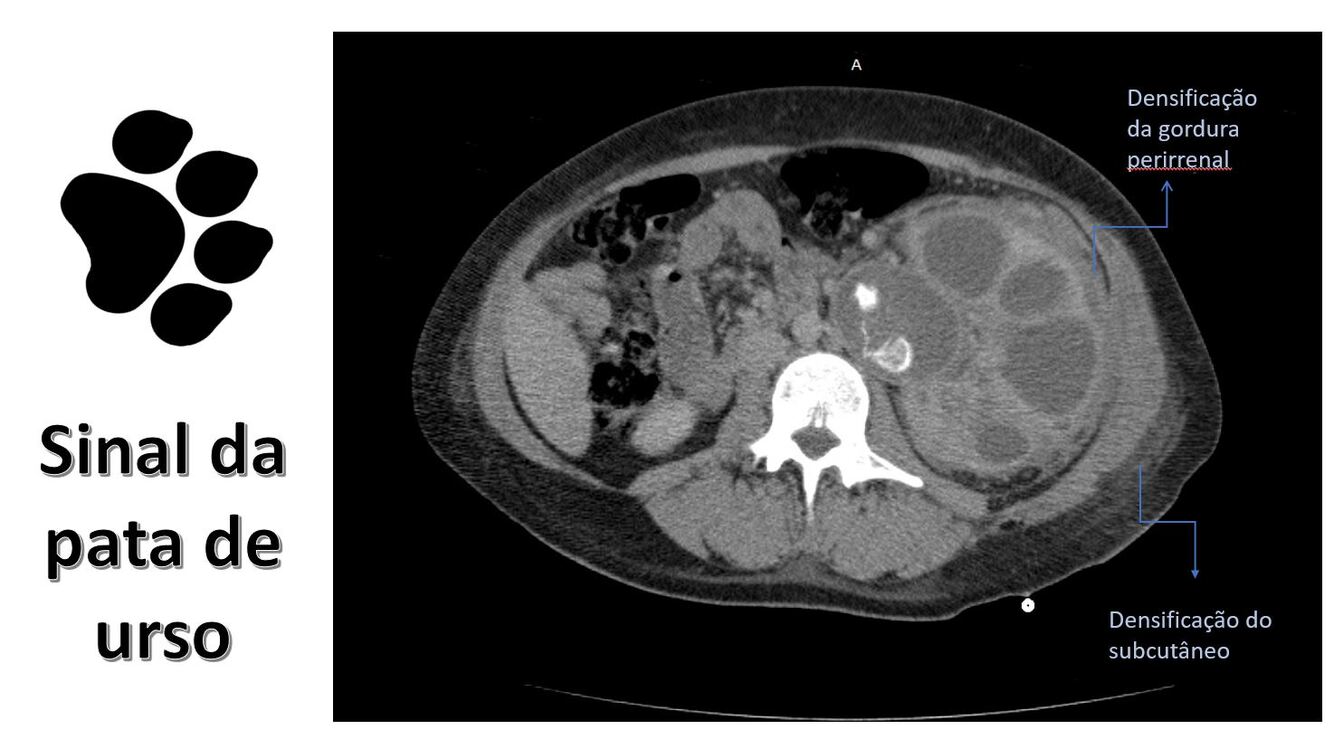

🟦 PIELONEFRITE XANTOGRANULOMATOSA

Infecção crônica, destrutiva, granulomatosa, quase sempre associada a obstrução urinária crônica + cálculo coraliforme + pionefrose.

É um rim não funcionante, substituído por tecido inflamatório, gordura e coleções purulentas.

🟦 TOMOGRAFIA — COMO RECONHECER UMA XGP

👉 Achado clássico: SINAL DA “PATA DE URSO” (BEAR PAW SIGN)

👉 Morfologia típica:

📌CAVIDADES HIPODENSAS

📌Realce periférico

📌Cálculo coraliforme

📌Rim aumentado, globoso, irregular

📌Áreas de gordura e necrose misturadas